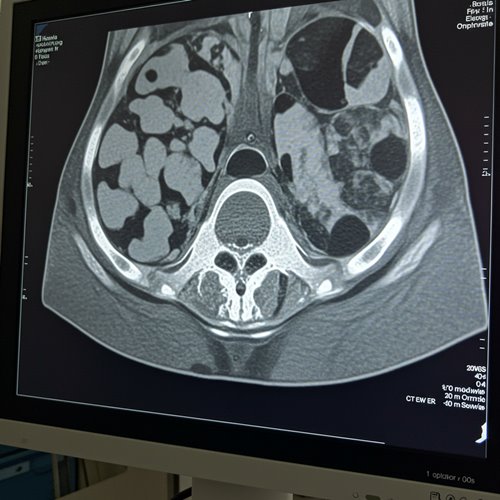

- 영상 검사: CT, MRI 등을 통해 암의 크기와 전이 여부를 평가합니다.